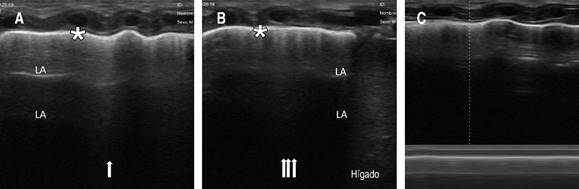

Dado que el neumotórax se consideró que era pequeño, solamente se mantuvo en vigilancia. Al día siguiente, en un nuevo UP ya no se observó, por lo que se determinó que el neumotórax se había resuelto (Figura 3). El paciente se extubó al quinto día y, al concluir ciclo de antibióticos, se egresó a su domicilio sin complicaciones.

Figura 3: Se realiza ultrasonido pulmonar (ultrasonido portátil lineal de 10 Hz) de control en el que se observa: A) pulmón anterior derecho apical y medial y B) pulmón anterior medial y basal derecho con líneas-B (flechas) que corroboran resolución del neumotórax y líneas-A (LA). C) El deslizamiento de la línea pleural se corrobora mediante el modo-M que demuestra el “signo de la playa”.